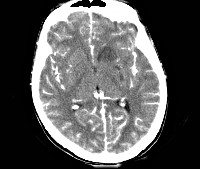

- МРТ головного мозга. Диагностирует гидроцефалию, при наличии масс-эффекта — смещение мозговых структур. Определяет повышение плотности оболочек, наличие в них мелких очагов. Более информативна МРТ с контрастированием, позволяющая выявить накопление контраста в оболочечных тканях, субарахноидальных пространствах.